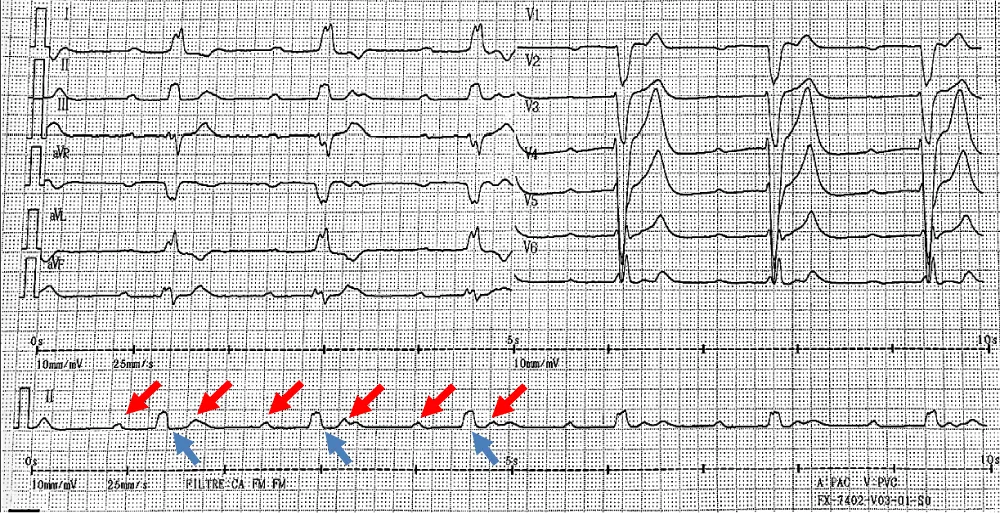

The next day, the patient presented hypotension and bradycardia. The ECG revealed a severe bradycardia (Figure 1, section A) with a complete atrio ventricular (AV) block and wide QRS complex. The blood sample was unchanged. An external pacemaker was implanted by right jugular access and the patient was transferred in a resuscitation care unit to receive ciclophoasphamide and corticosteroid therapy associated to plasma exchange. Few days after immunotherapy, surface ECG showed a sinus tachycardia with normal atrioventricular conduction and narrow QRS complex (Figure 1, Section B).

Figure 1: Section A: Third degree atrioventricular block with complet dissociation between P waves (red arrows) and QRS complexes (blue arrows).

Figure 1: Section B: Sinus rhythm with normal atrioventricular conduction four days after immunotherapy.